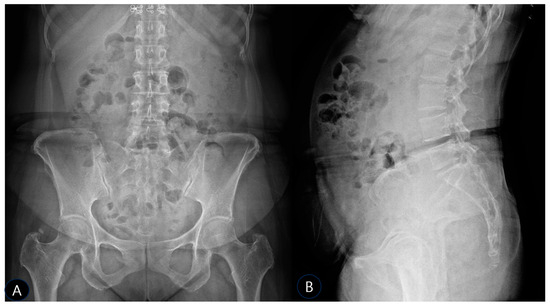

Background: Deep gluteal syndrome (DGS) is an underdiagnosed cause of sciatica-like pain, involving the entrapment of the sciatic nerve by various structures within the subgluteal space. While cases of ossification or calcification in the context of severe pelvic imbalance have been rarely reported, isolated SSL calcification as a primary cause of DGS remains largely unexplored and undocumented. This case report presents the first documented instance of sacrospinous ligament (SSL) calcification identified as the primary cause of DGS and its successful management with ultrasound-guided prolotherapy. Case Presentation: A 51-year-old female presented with severe, worsening left-sided sciatica of several months’ duration. Physical examination revealed an antalgic gait, positive sacroiliac joint tests, and multiple positive DGS-specific provocative tests (FAIR, Pace sign, Seated Piriformis Stretch). Radiographs and musculoskeletal ultrasound (MSK-US) confirmed calcification within the left sacrospinous ligament, with associated sciatic nerve swelling. The patient underwent three sessions of ultrasound-guided prolotherapy (dextrose 10% with lidocaine) targeting the calcification site, followed by a structured rehabilitation program. Results: The patient reported a significant reduction in pain, from a Visual Analog Scale (VAS) score of 10/10 to 1/10 within one month. All previously positive provocative tests converted to negative, indicating a resolution of the nerve entrapment. Functional mobility was fully restored. Conclusions: This case highlights isolated sacrospinous ligament calcification as a potential and previously overlooked pathological entity responsible for deep gluteal syndrome. To our knowledge, this is the first report to implicate ligamentous calcification as a primary etiological factor in DGS. Musculoskeletal ultrasound proved indispensable for both diagnosis and treatment guidance. Furthermore, ultrasound-guided prolotherapy emerged as a successful and minimally invasive therapeutic option in this case, potentially by stabilizing the ligament and reducing neurogenic inflammation. This case expands the differential diagnosis of sciatica, introduces a new target for intervention in refractory cases, and underscores the need for future studies in larger patient cohorts to validate these findings. Full article

Figure 1